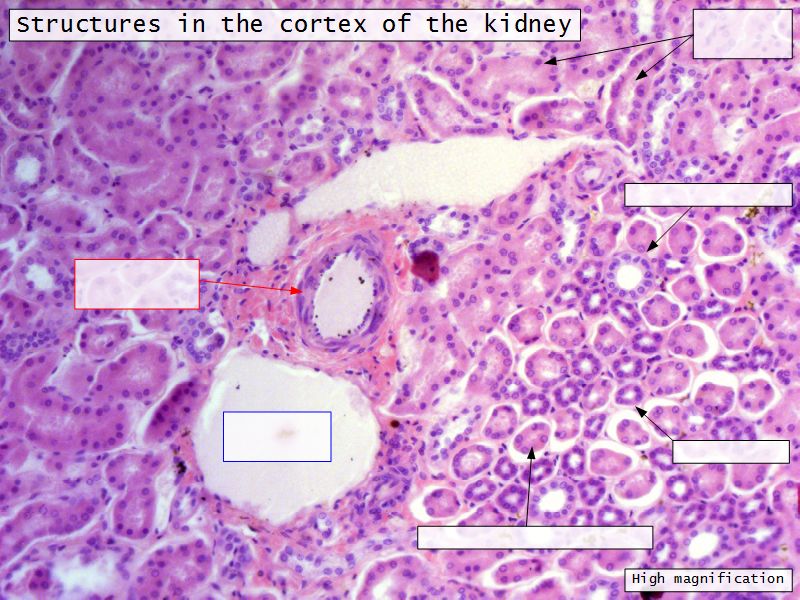

Appearance

- Cortex

- Renal corpuscles

- Convoluted tubules

- Medulla

- Loops of Henle

- Collecting tubules

Kidney lobule

- Group of neprons

- Open into branches

- Same collecting duct

- Not clearly demarcated

- Interlobular arteries/veins